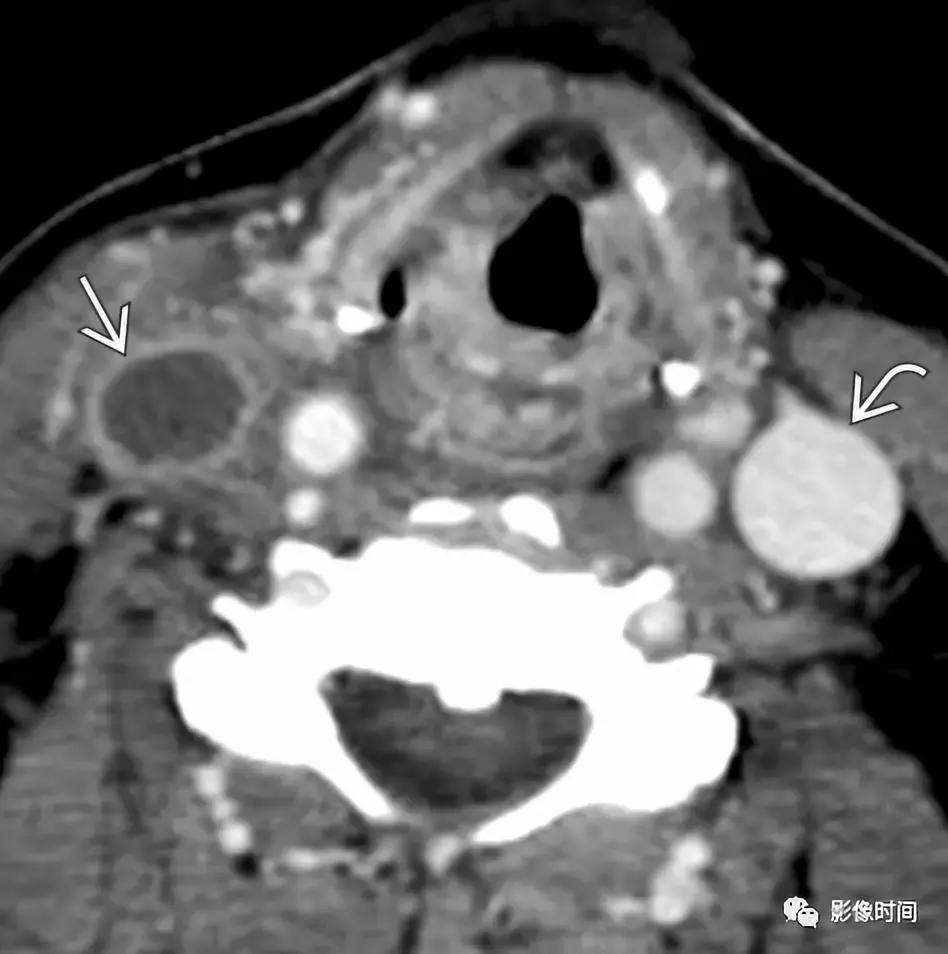

7.短暂颈动脉周围炎症:也称为 Fay 综合征,患者多表现为单侧颈总动脉分叉区域持续性搏动疼痛,具有自限性,往往 1-2 周缓解,首选激素治疗。虽然目前发病机制存在争议,但是大多数认为与颈总动脉分叉区域的特发性炎症有关,因此,又被称为短暂颈动脉周围炎症。CT、MRI 显示颈动脉周围软组织异常、劲动脉壁增厚,特别是分叉处,管腔一般不受影响,CT 一般为低密度,T1WI 压脂序列呈稍低信号(区别于夹层高信号),增强扫描呈明显强化,激素治疗随访后消失。

CTA 显示轴向左侧颈总动脉分叉区周围软组织增厚(无尾箭头),管腔未见狭窄,可见软斑块(长箭头)。TOFMRA 显示左颈内动脉周围软组织增厚,注意右颈内动脉的正常外观。冠状 T1WI+C 显示左侧颈内动脉周围明显强化 (长箭头),注意右颈内动脉的正常外观。激素治疗随访约 4 个月后,冠状 T1WI+C 显示颈内动脉周围厚度减轻。